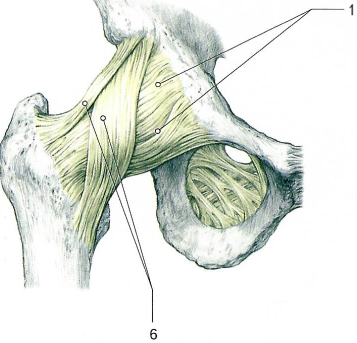

Тазобедренный сустав по строению простой, по форме шаровидный (чашеобразный), по функции многоосный.

Сустав образован полулунной поверхностью вертлужной впадины тазовой кости (имеет вертлужную губу[2]) и головкой бедренной кости.

В суставе возможны сгибание и разгибание, отведение и приведение, пронация и супинация, круговые движения бедра.

Связки, укрепляющие тазобедренный сустав.